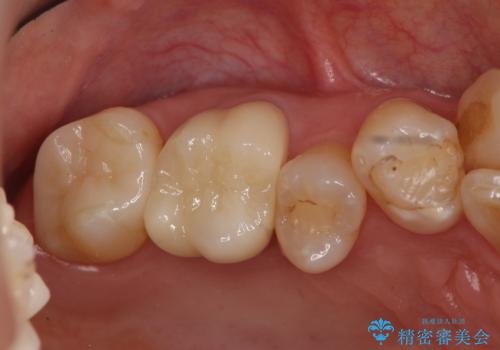

銀歯と、プラスチックをセラミックにかえました。

- 合計 19.8万円 右上7:セラミックインレー 7万円、右上6:ジルコニアクラウン10万円、仮歯1万円費用は治療当時の料金となります

右上6番は詰め物が大きく、インレーではなくクラウンとしました。